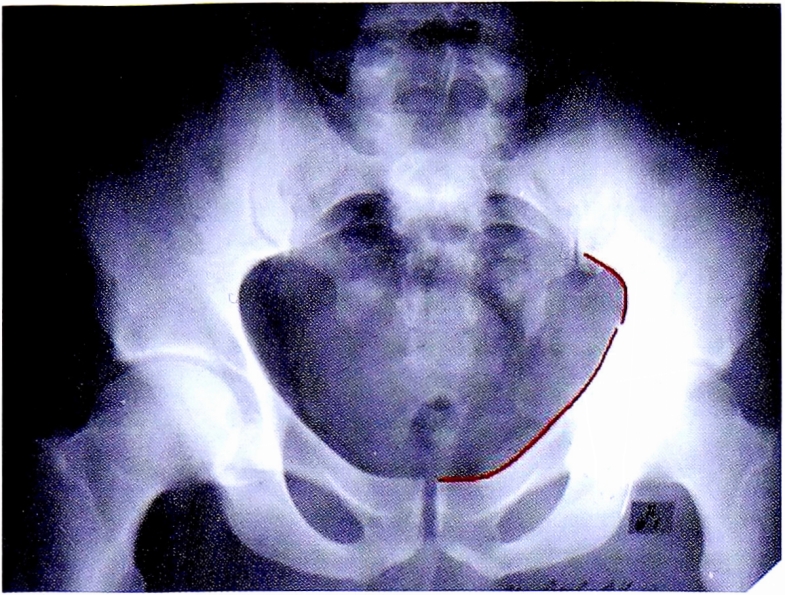

На прямой обзорной рентгенограмме, представленной на рис. 22, целостность подвздошно-седалищной линии сохранена. Данный признак позволяет исключить повреждение структур задней колонны. По классификации Judet—Letournel мы можем исключить следующие переломы: поперечный перелом вертлужной впадины, поперечный ассоциированный с переломом задней стенки, Т-образный, передней колонны, ассоциированный с задним полупоперечным, двухколонный перелом (при которых заинтересованы обе колонны.

Непрерывность подвздошно-седалищной линии позволяет, кроме того, исключить: перелом задней колонны, перелом задней колонны, ассоциированный с переломом задней стенки (см. рис. 22).

Рис. 22. Первый этап определения перелома передней стенки.

Fig. 22. First step of anterior wall fracture diagnostic.

Важно отметить, что сохранение непрерывности контура запирательного отверстия позволяет исключить перелом передней колонны (рис. 23).

Рис. 23. Второй этап определения перелома передней стенки.

Fig. 23. Second step of anterior wall fracture diagnostic.

Непрерывность контура заднего края вертлужной впадины позволяет исключить перелом задней стенки (рис. 24, а).

Нарушение непрерывности только подвздошногребешковой линии позволяет заподозрить перелом передней стенки (см. рис. 24, б).

Рис. 24. a — интактные референтные линии; б — комбинация референтных линий.

Fig. 24. а — intact reference lines; b — combination of reference lines.

Таким образом, методом исключения диагностирован перелом передней стенки.

Рентгенограмма в косой подвздошной проекции подтверждает перелом передней стенки вертлужной впадины (рис. 25).

Рис. 25. Окончательное определение и верификация перелома передней стенки.

Fig. 25. Final diagnostic and verification of anterior wall fracture.